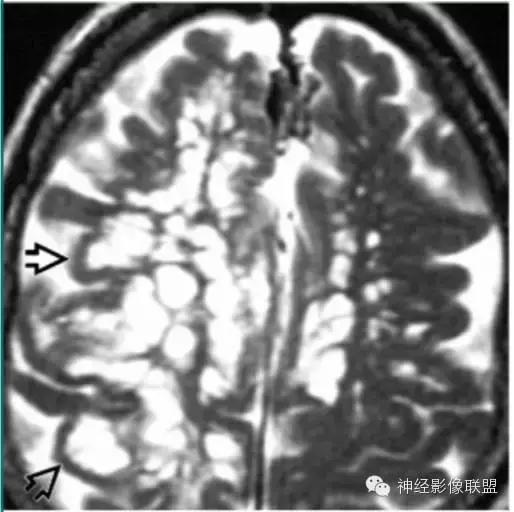

神经胶质囊肿